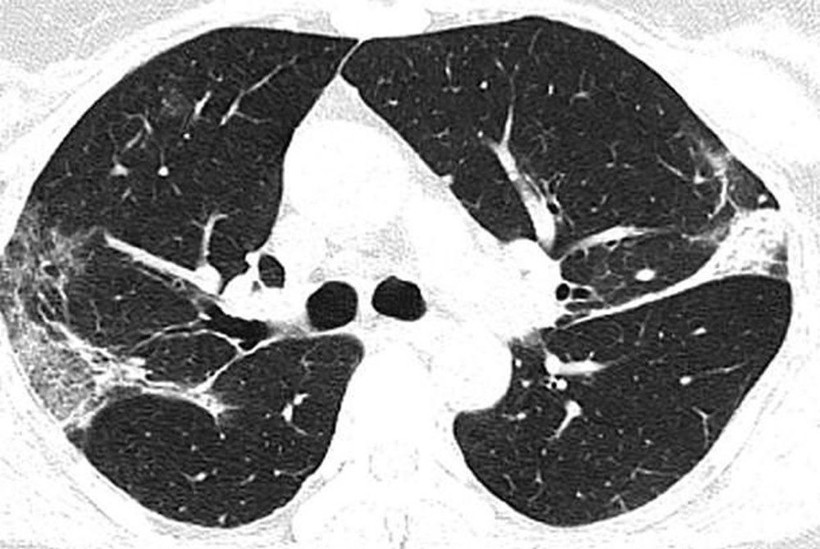

Filmlerde akciğerdeki hava boşluklarının çoğunluğunun virüs nedeniyle dolduğu görülüyor. Uzmanlar, taramalarda görülen beyaz lekelerin SARS ve MERS’te de mevcut olduğunu belirtti. Kuzey Amerika Radyoloji Derneği (RSNA), yeni tip corona virüsün (Covid-19) ortaya çıktığı Çin’in Wuhan kentindeki salgının kaynağı olduğu düşünülen deniz ürünleri pazarında çalışan ve 44 yaşında virüs nedeniyle hayatını kaybeden bir adamın röntgen filmlerini kamuoyuyla paylaştı.

Filmlerde corona virüsün akciğerleri nasıl tahrip ettiği net bir şekilde görülüyor. X-ray ışını taramalarında corona virüsün etkileği yerler beyaz olarak görülüyor. Uzmanlar, hastada virüsün akciğerlerdeki hava keseciklerini kısmen doldurduğunu ve akciğer nodüllerine sebep olduğunu belirtti. Diğer taraftan aynı tip anormalliklerin SARS (Şiddetli Akut Solunum Sendromu) ve MERS (Ortadoğu Solunum Sendromu) vakalarında da görüldüğünü söylediler.

Diğer taraftan, A görüntüsüyle F görüntüsü karşılaştırıldığında, akciğer uzuvlarında bulunan sıvının, zaman içinde belirgin bir şekilde corona virüs nedeniyle arttığı görülebiliyor. Röntgenleri paylaşılan adamın yaklaşık iki hafta boyunca ateş ve öksürük belirtileri göstermesinin ardından 25 Aralık 2019'da hastaneye kaldırıldığı bir hafta sonra ise hayatını kaybettiği açıklandı.